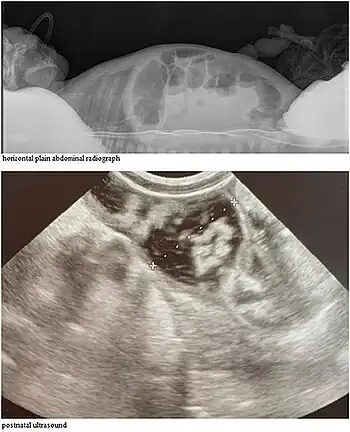

CCD causes persistent secretory diarrhea. In a fetus, it leads to polyhydramnios and premature birth. Immediately after birth, it leads to dehydration, hypoelectrolytemia, hyperbilirubinemia, abdominal distention, and failure to thrive.[3]

CCD may be detectable on prenatal ultrasound.[4][5]

After birth, signs in affected babies typically are abdominal distension, visible peristalsis, and watery stools persistent from birth that show chloride loss of more than 90 mmol/L.[5]